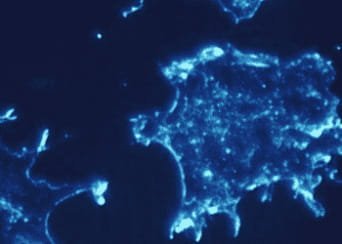

Ricercatori del San Raffaele hanno identificato il meccanismo con cui le cellule tumorali sfuggono al sistema immunitario successivamente all'intervento di trapianto

Ricercatori del San Raffaele hanno identificato il meccanismo con cui le cellule tumorali sfuggono al sistema immunitario successivamente all'intervento di trapianto